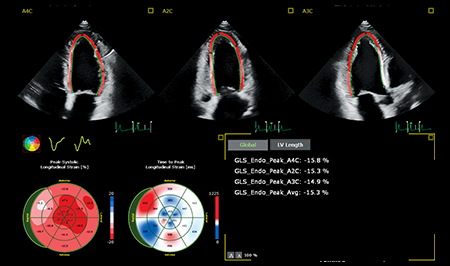

Reconnaissance automatique des incidences, placement automatique du contour, suivi du Speckle, cet outil permet une mesure GLS robuste et reproductible en un seul clic.

En tant que cardiologue, vous devez poser des diagnostics de façon rapide, sûre et reproductible. La nouvelle solution Philips Affiniti CVx, associe l’expérience de Philips dans le domaine de la cardiologie et l’expertise éprouvée de TOMTEC en matière de quantification.

Le nouvel Affiniti CVx intégre de nombreux outils TOMTEC de quantification automatisée sur lesquels vous appuyer: 3D Auto MV, 3D Auto LAA et AutoStrain LV. Ces outils vous offrent des mesures fiables et reproductibles nécessaires à différentes étapes de la prise en charge de vos patients.